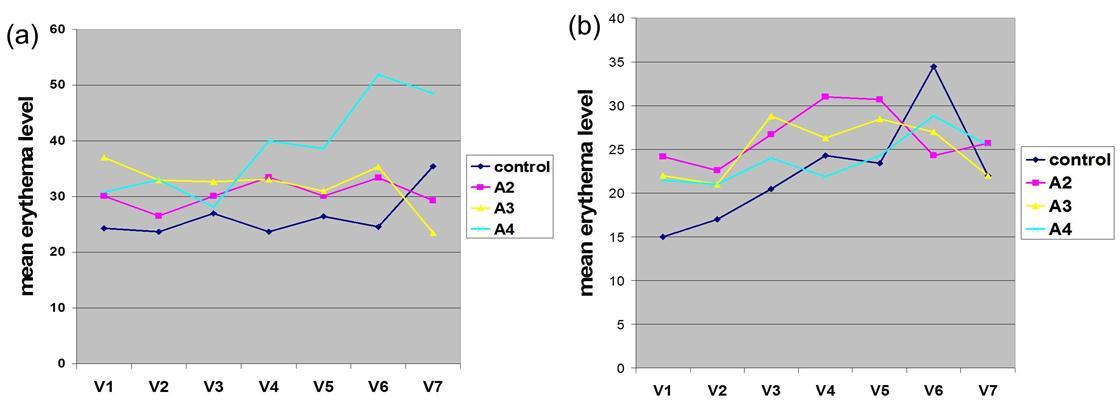

In contrast to IQM alone, the combined use of the fractionated erbium:YAG laser microporation with IQM dominantly induced stronger skin erythema levels starting from visit V2 throughout the last visit V20 (Figure 3a). For the stronger therapeutic responses of crusting and erosions this phenomenon was even more pronounced. By looking at the mean crusting PGA values of V2, V4 and V7 together as early time point of the therapy, arm 2-4 presented with the scores of 0.76±0.3, 1.25±0.2 and 1.3±0.5 compared to the much less pronounced value of crusting in the single IQM control arm-1 with 0.3±0.2. The same is true for the late therapy time point V9/11/13/20 with crusting 2.25±0.8, 2.5±0.5 and 2.3±0.4 arms 2-4 and only 1.3±0.6 in the control arm. For erosions the following mean PGA scores were delineated: V2/4/7 arm 1-4 0.08±0.1, 0.6±0.3, 0.75±0.2, 0.95±0.5 and V9/11/13/20 arm 1-4: 0.5±0.25, 1.2±0.6, 1.37±0.3, 1.44±0.4. Regarding the IQM skin responses no correlation could be found with the amount of shots and pulses used by the laser device. Histopathology of V20 lesional punch biopsies showed in all BCC a dense infiltrate of inflammatory cells which is typical for an adequate IQM response. When this infiltrate was fully replacing signs of BCC the lesions were defined as fully cleared (Figure 4). Within arm 2-4 BCC lesions cleared at 33% (persistent 1 nodular and 1 superficial BCC), 100% and 100% at V20, respectively. Taken together IQM alone led to clearence of 3 out of 4 (75%, persistent a superficial) BCC, though the treatment period was shortened from 6 to 3 weeks. The combined fractionated erbium:YAG laser and IQM application resulted in a slightly better clearance rate of 14 BCC vs. 4 (78%). Notably, those 2 BCC patients, where the laser and IQM application was stopped at V11 also showed full clearence. Figure 5 presents the typical treatment course of a patient in arm 3. Tolerability of the laser microporation was excellent with slight burning or the feeling of small needle sticks during the application. In addition, microporation did not cause any immediate irritation of the skin. Even when erythematous, crusted or eroded IQM lesions were microporated the good tolerability stayed the same. No severe adverse or adverse reactions were noted.

Figure 3.Course of skin erythema:a) Basal cell carcinoma study.b) Actinic keratosis study.

As seen in the treatment of BCC, AK microporation with IQM also led to essentially the same stronger skin erythema (with one unique peak at V13 in the control arm 1) compared to IQM alone (. Figure 3b). In addition, mean PGA scores for crusting and erosion of control arm 1 in relation to arms 1-4 were just lower in the beginning of the therapy (mean PGA at V2/4/7-arm 1-4 for crusting: 0.42±0.3, 0.83±0.3, 1.12±0.1, 1.16±0.1; erosion: 0±0, 0.3±0.2, 0.43±0.2, 0.41±0.1) and reached the same levels towards the end (mean PGA at V9/11/13/20-arm 1-4 crusting: 1.5±0.3, 1.5±0.2, 2.15±0.1,1.7±0.3; erosion: 0.7±0.1, 0.6±0, 1.2±0.1, 0.71±0). In arm 2 50% of AK lesions, in arm 3 100% and in arm 4 75% cleared. Taken together, the clearence rate in the fractionated erbium:YAG laser plus IQM arms counted for 75% or 10 AK vs. 50% or 2 AK in the control arm. One patient from arm 2 was followed up to 6 months and showed no relapse of AK (Figure 6). Tolerability of the laser microporation device was the same as seen with BCC treatment and no sever adverse reactions were noted.

IQM effects on microporated skin, i.e. the nature and quality of the therapeutic skin reactions erythema, crusting and erosions are essential to understand the efficacy of this new therapeutic approach. Erythema representing the most solid IQM reaction appeared already after day 2 and initially was stronger compared to erythema in skin treated with IQM alone. Notwithstanding this early strong reaction, at the later phase of the therapy (V11/13/20) levels of skin erythema in microporated and non-microporated skin were essentially the same. By looking at the more pronounced IQM skin reactions such as crusting and erosions, in AK their behaviour was comparable to erythema, while in BCC their late phase strength was also stronger than IQM alone. Based on the IQM mode of action, it seems obvious that the differences in the therapeutic skin reactions might be caused by the application of IQM via the micropores which leads to a faster and closer IQM contact with the epidermal dendritic cells. Based on this mechanism, we would suggest to call the combined therapeutic use of the fractionated erbium:YAG laser microporation with IQM “laser dynamic therapy (LDT)”.